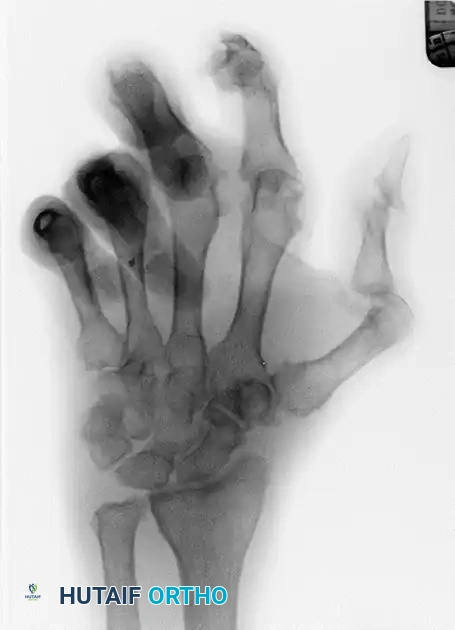

FIGURE 5: Right hand demonstrating limited finger flexion following metacarpophalangeal joint resection arthroplasty in a psoriatic patient.

FIGURE 6: The same right hand demonstrating limited finger extension. Postoperative stiffness remains a significant challenge in psoriatic arthroplasty.